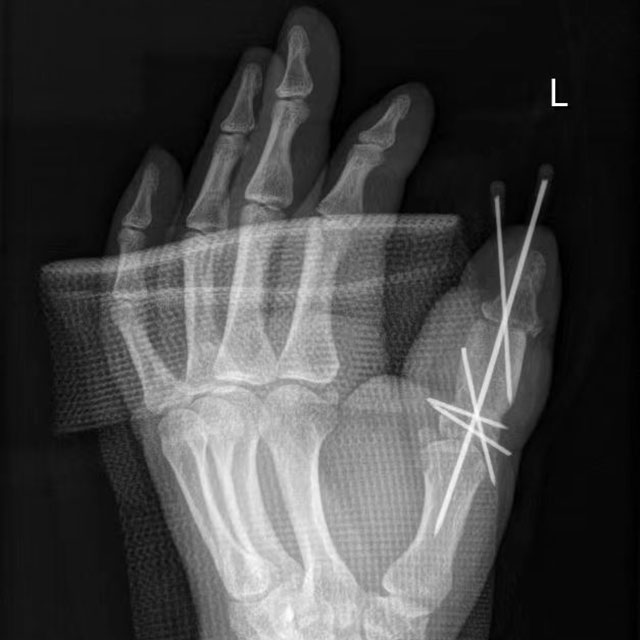

骨伤科手外·儿骨·烧伤整形组副主任(主持工作)陈孝均组织团队讨论后,决定行“左手拇指复合组织重建”,即在赵大哥左侧腹股沟处切除7×5×3cm复合骨皮瓣,将皮瓣动脉与鼻烟窝桡动脉呈端侧吻合,皮瓣静脉与皮下静脉吻合。

陈孝均介绍:“截取出的髂骨接到拇指上会在一定程度被吸收,所以我们骨块打磨比正常拇指骨块略粗,避免被吸收后的骨块太细容易骨折。另外,髂骨瓣的供区对患者没有太多的影响,所以不必太担心。”

术后一个月,赵大哥来医院复查,恢复得很好。再过段时间,便可以取出钢钉,进行康复训练了。